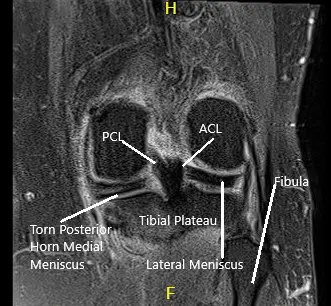

An MRI of the left knee suggested osteoarthrosis with high-grade cartilage loss in the medial compartment and high-grade cartilage loss central trochlear cartilage with low-grade chondral loss patellar cartilage. Large radial tear posterior horn medial meniscus which is peripherally extruded. There is a loose body in the deep aspect of Hoffa’s fat pad measuring 4 mm x 8 mm.

MRI of the left knee showing axial and coronal sections.